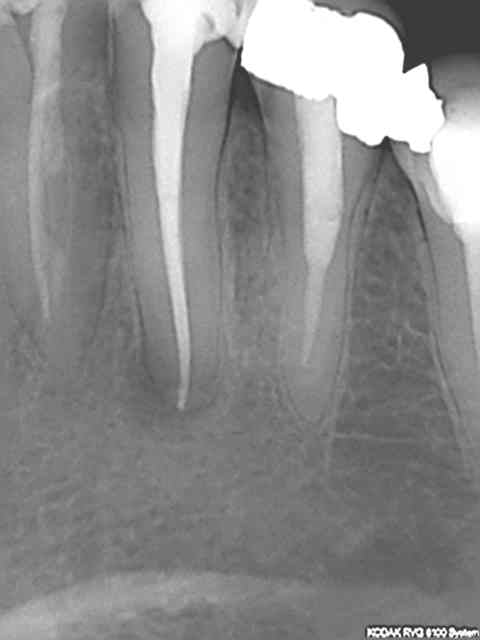

T'inquiètes il y en a qui ne sont pas stressés. On essaye de remonter le niveau, rien de sorcier il suffit de disposer du matos adéquat, endo master + S1 protaper et wd gold + R25 réciproc pour moi, Résultats reproductibles à 100%. La dernière de ce soir avant et après, un jeu.

Mais on est pas à l'abri d'un peuf à l'apex comme tout de suite. Arghhh, je ne vais pas en dormir !)))))))

Pas de digue sur ce coup ci, car paroi vestibulaire inexistante et 30 mn pour faire l'endo (dont 15 à l'endo activator et ca c'est long !)

PPS : chicot y'a du boulot sur les dents d'à côté je crois hehehe.